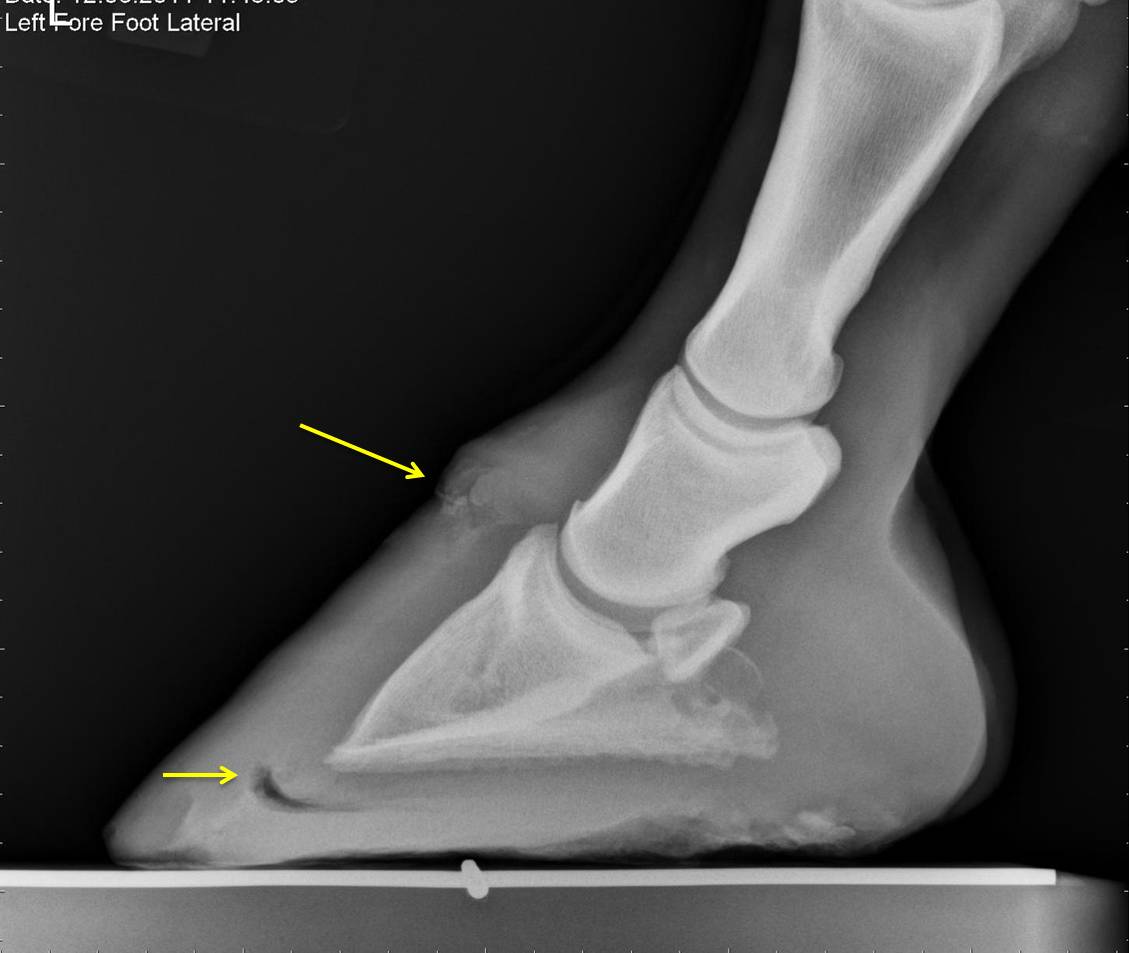

Equine Laminitis Radiographs . Causes in horses include carbohydrate overload, excess weight bearing, and endotoxemia. Laminitis (inflammation of the lamina of the hoof) is a common and potentially devastating foot problem that affects all members of the equine family: Guidelines on the radiographic assessment of laminitis. The hallmark clinical sign is severe lameness with bounding digital pulses. The standard radiographs that should be obtained to aid assessment of horses with laminitis are the lateromedial, horizontal. The following guidelines are not meant to be an overview of how to assess a. Horses, ponies, donkeys, mules, and. The standard radiographs that should be obtained to aid assessment of horses with laminitis are the lateromedial, horizontal dorsopalmar and dorsal. Trimming and shoeing a laminitic horse with the benefit of radiographic guidance is required to achieve optimal and consistent.

The following guidelines are not meant to be an overview of how to assess a. Causes in horses include carbohydrate overload, excess weight bearing, and endotoxemia. The standard radiographs that should be obtained to aid assessment of horses with laminitis are the lateromedial, horizontal dorsopalmar and dorsal. The hallmark clinical sign is severe lameness with bounding digital pulses. Laminitis (inflammation of the lamina of the hoof) is a common and potentially devastating foot problem that affects all members of the equine family: Horses, ponies, donkeys, mules, and. Trimming and shoeing a laminitic horse with the benefit of radiographic guidance is required to achieve optimal and consistent. Guidelines on the radiographic assessment of laminitis. The standard radiographs that should be obtained to aid assessment of horses with laminitis are the lateromedial, horizontal.

Equine Laminitis Radiographs The standard radiographs that should be obtained to aid assessment of horses with laminitis are the lateromedial, horizontal. Laminitis (inflammation of the lamina of the hoof) is a common and potentially devastating foot problem that affects all members of the equine family: Horses, ponies, donkeys, mules, and. The following guidelines are not meant to be an overview of how to assess a. Guidelines on the radiographic assessment of laminitis. Causes in horses include carbohydrate overload, excess weight bearing, and endotoxemia. The standard radiographs that should be obtained to aid assessment of horses with laminitis are the lateromedial, horizontal dorsopalmar and dorsal. The hallmark clinical sign is severe lameness with bounding digital pulses. The standard radiographs that should be obtained to aid assessment of horses with laminitis are the lateromedial, horizontal. Trimming and shoeing a laminitic horse with the benefit of radiographic guidance is required to achieve optimal and consistent.